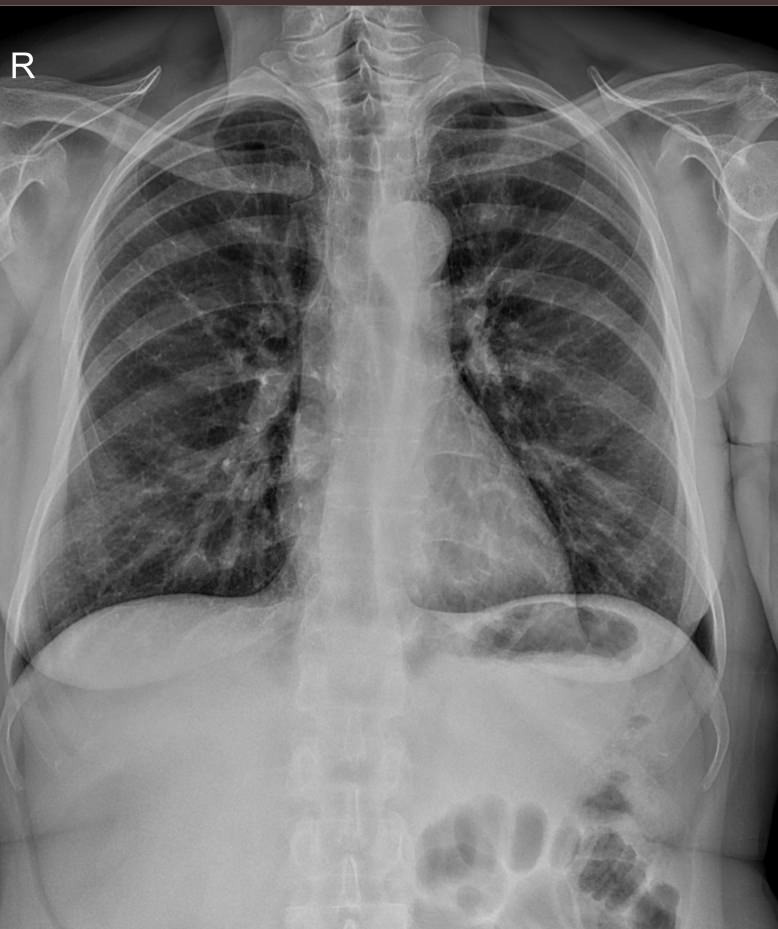

В качестве основного метода исследования при патологии ребер назначают рентгенодиагностику. Это простой и доступный способ узнать состояние костной ткани изнутри, не нарушая целостности кожных покровов. минимальная доза излучения современных рентгеновских аппаратов делает рентгенографию безопасной.

Что покажет рентген ребер (прицельно)

На рентгенограмме будут видны:

• Перелом и его локализация;

• Отек, отломки и осколки кости и инородные тела в мягких тканях;

• При рентгене верхних ребер ― возможные повреждения тканей легких, трахеи, пищевода;

• При обследовании нижних ребер ― повреждение тканей и органов верхней части живота: печени, селезенки, почек, диафрагмы.